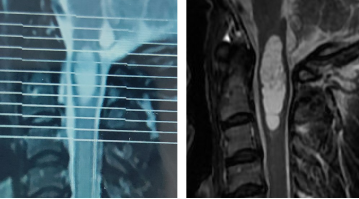

图2  张先生2016年(左)和2020年(右)核磁图像,提示肿瘤明显增大

图3 张先生在我院复查的核磁,病变范围从延髓到颈3椎体上缘